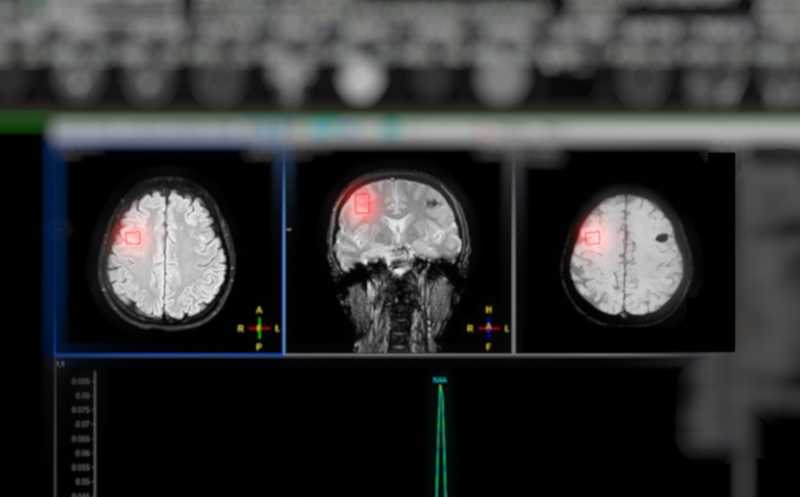

Нормальное функционирование мозга — необходимое условие жизни человека, поэтому его способность восстанавливаться после повреждений крайне важна. У взрослых млекопитающих нишей стволовых клеток, обеспечивающих образование новых функциональных нейронов, служит субвентрикулярная зона (СВЗ). Новые нейроны образуются в ней из нейральных стволовых клеток-предшественников (NSPC), а затем мигрируют в пораженные области. Однако после инсульта процесс нейрогенеза значительно ограничен, и причины этого пока неясны. Команда из Фрайбургского университета (Германия), поставила перед собой задачу изучить механизм, лежащий в основе этого ограничения.

Исследование проводили на мышиной модели фототромботического инсульта. (Мышам вводили внутрибрюшинно светочувствительный краситель, а потом небольшой участок коры мозга освещался в течение нескольких минут.)